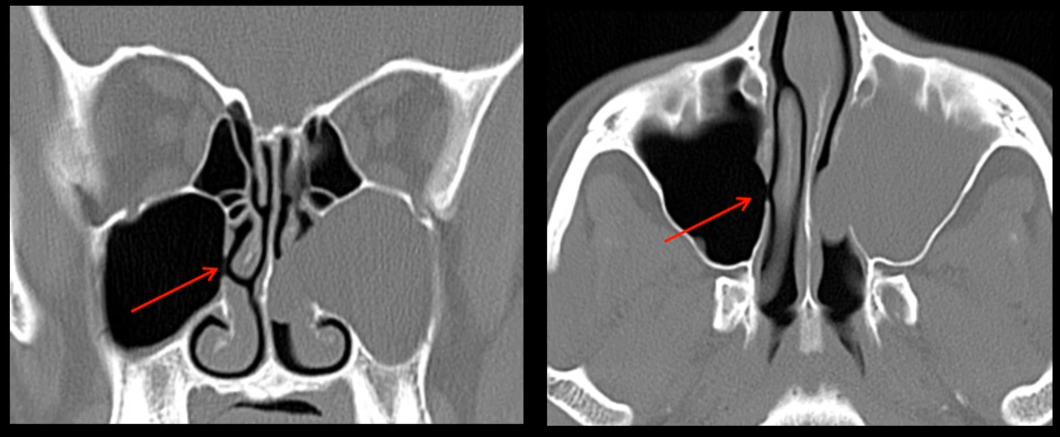

• Type de polype nasal

• part du sinus maxillaire, s’étend dans la cavité nasale

• Elargissement de l’ostium